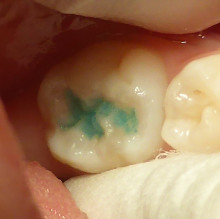

まず 汚れをおとして 薬で消毒です

次に、この 青いクスリを洗い流して